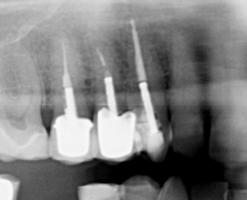

On your initial appointment the dentist will locate the offending tooth and take an x-ray in order to show the roots of the tooth, to see how far the decay has travelled and if there is an abscess present. A course of antibiotics may be given to clear the abscess before the treatment is started as the abscess will reoccur if the treatment is NOT carried out.

• Once access has been gained to the pulp chambers the dead pulp is removed from the root canals using very small files and a hydrochloric wash. An additional x-ray will be taken at this point.

• An X-ray is then taken to check that the canals have been filled completely.